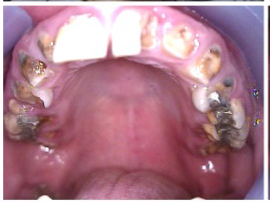

The patient in Figure 10 through Figure 12 was pregnant when she presented for dental treatment. The pregnancy was unplanned and she had had a lack of prenatal care. Continuing meth use during the pregnancy resulted in a positive toxic baby. She stated that she had just stopped using meth and had entered a rehabilitation facility a few days before. She was brought to the author’s clinic with a toothache. Note that as seen in these images, extreme accumulation of plaque, lack of oral hygiene, and severely decayed and missing teeth are classic manifestations in meth users.

Fig 10. Accumulation of soft plaque is typical of oral hygiene neglect associated with the use of methamphetamine.

Fig 11. Note demineralization of smooth surfaces, carious lesions at the gingival margins, and associated inflammation of the periodontium.

Fig 12. Radiographs of patient in Fig 10 and Fig 11 illustrating nonrestorability of the dentition.